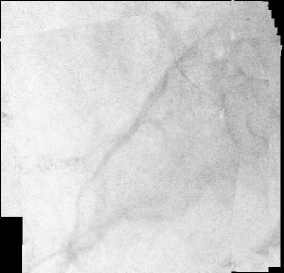

Figures 4 and 5 show two panoramic images constructed from real cystoscopic examination images using and respectively. The panoramic image in Figure 4 is a 1479 1049 pixel image constructed from a 450 image sequence using . In this panoramic image, two polyps are visible on the top-right and at the bottom left of the image. Both polyps can be accurately located in relation to each other. Figure 5 represents a 650 182 pixel panoramic image constructed from a 500 cystoscopic image sequence using . There are no visible discontinuities on texture affirming a quite good visual coherence.

and were programmed in C language using OpenCV vision library. The evaluation of both algorithms robustness and accuracy was done using an Intel Dual core(TM) 2.40GHz, 2Gb RAM computer. The optimization method of the algorithm requires, in average, 250 iterations to register consecutive images. And each image pair registration takes between 50 and 60 seconds. In Figure 5, the construction of the panoramic image took nearly 8 hours 27 minutes. However, in the same experimental conditions, is about 100 times faster than . In fact, a mean number of 12 iterations was needed by the optimization algorithm of the algorithm to register a pair of images. The time of registration for an image pair varied between 0.3 and 0.6 second. The panoramic image shown in Figure 4 was constructed in 3.20 minutes. The computation time of the makes possible the construction of partial panoramic image of the bladder during the standard cystoscopic examination procedure.